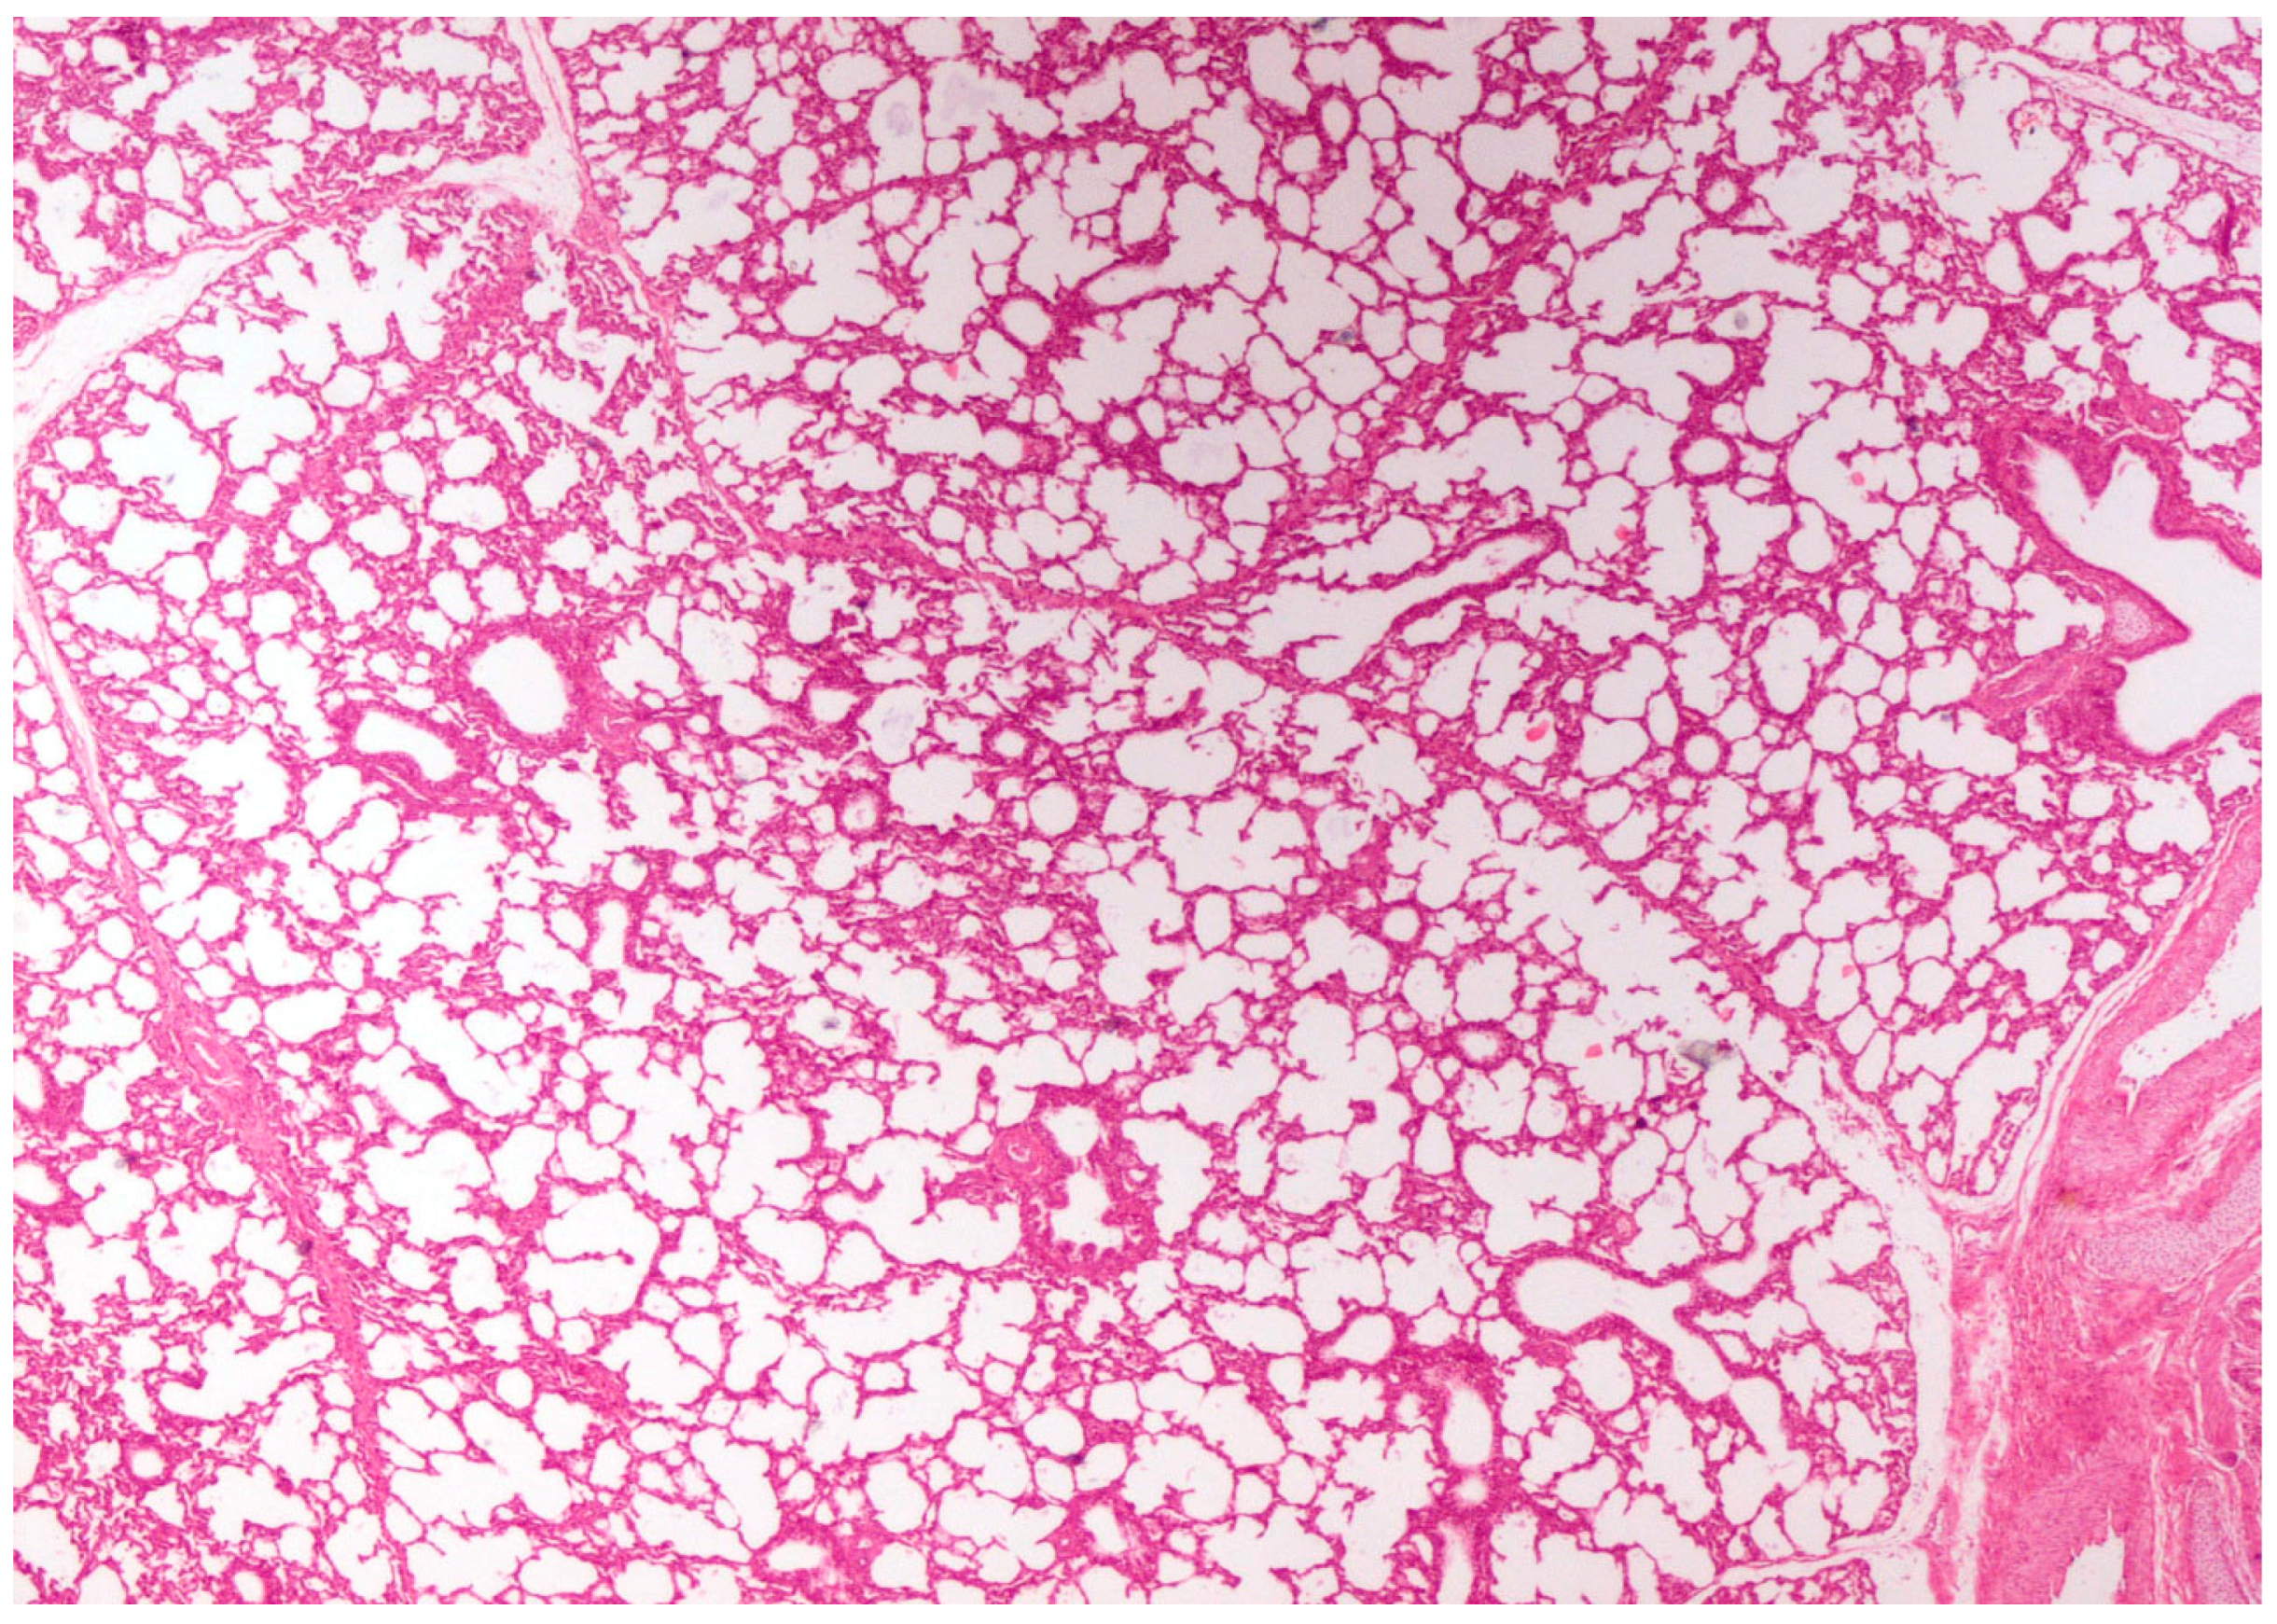

3.3.2. Histopathological Lesions

3.3.3. Scanning Electron Microscopy (SEM) Findings